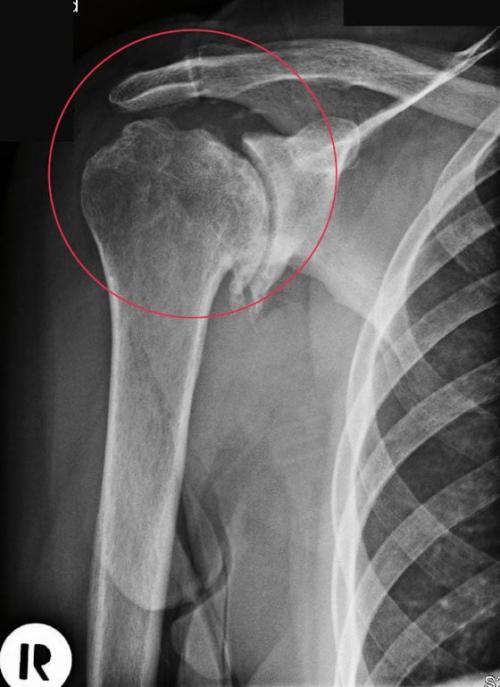

Верхние конечности — это сложно организованное сочленение костей. Они обеспечивают трудоспособность человека и позволяют выполнять различные манипуляции руками. Щелкает плечевой сустав при разных заболеваниях позвоночника, соединительной и хрящевой ткани непосредственно самого сустава. При первичном осмотре, если щелкает и болит плечевой сустав, врач старается исключить также разрывы связок и плечелопаточный периартрит. Детальная диагностика позволяет точно определить источник неприятных ощущений и поставить верный диагноз. Рекомендуется сделать рентгенографический снимок, компьютерную томограмму или, в случае неэффективности данных методов диагностики, артроскопию плечевого сустава. В ходе этой манипуляции может быть проведено хирургическое эндоскопическое вмешательство с целью восстановления структуры связочного сухожильного аппарата.

Обратите внимание на неровные края головки плечевой кости.

Если звуки появляются нечасто и пока не сопровождаются болью, то вполне возможно повернуть патологический процесс вспять. В терапевтические схемы врачи включают НПВС (Нурофен, Фастум, Вольтарен ) в виде мазей, гелей. Обязательно назначается курсовой прием хондропротекторов (Терафлекс, Структум, Артра) в течение нескольких месяцев, физиопроцедуры ( лазеротерапия , бальнеолечение, УВЧ-терапия), регулярные ежедневные занятия лечебной физкультурой.

Реальное фото пораженной хрящевой поверхности.

Боль, возникающая одновременно со щелчками, является информативным симптомом прогрессирования остеоартроза и повреждения значительной части гиалинового хряща. На этой стадии уже невозможно полностью восстановить разрушенные ткани, поэтому основной задачей терапии становится предотвращение распространения патологии. Для устранения болей применяются таблетки с НПВС (Нимесулид, Вольтарен, Ибупрофен), а при их неэффективности — глюкокортикостероиды (Кеналог, Гидрокортизон, Преднизолон). После достижения устойчивой ремиссии пациенту рекомендуется избегать нагрузок на плечевой сустав и заниматься лечебной физкультурой.